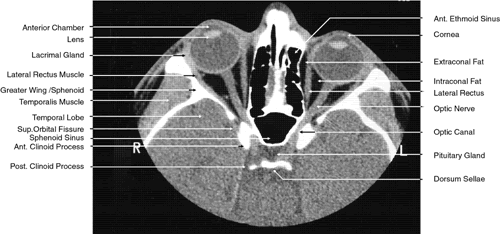

2D CT imaging is most frequently performed in the axial plane (Fig. 2). The bony anatomy of the orbit, optic canal, and intracranial cavity determines the exact orientation of this plane to provide the best visualization of both bone and soft tissue. The bony orbit is shaped like a quadrilateral pyramid lying on its side and with its base facing anteriorly. The medial orbital walls are almost parallel, although they tend to converge toward the midline in their posterior aspect. The lateral orbital walls diverge at approximately 45 degrees to the midline. The orbital axis is about 23 degrees divergent from the midline. The orbitomeatal line (Reid's baseline or the Frankfurt-Virchow line) is an important radiologic landmark for imaging the orbital structures. It is a line that extends from the upper margin of the external auditory meatus to the inferior orbital rim. The orbital floor is at approximately a -20-degree angle with this line, and the optic canal is at approximately a -30-degree angle with this line. Axial scans of the orbit are performed parallel to the orbitomeatal line, in contrast to axial scans of the intracranial contents, which are performed in a plane parallel to the orbital roof, which is at a + 30-degree angle to this line. The optic chiasm is also best imaged in a plane parallel to the orbitomeatal line. Although both the optic canal and nerve can be adequately visualized with axial scans parallel to this plane, scans of these structures are more precisely performed if the image plane is at a -30-degree angle to this line with the globe in upward gaze. This straightens the nerve and places its axis in the same plane as the canal. The optic canal of infants and young children is at approximately a -20-degree angle with the orbitomeatal line, and in these age groups the scanning angle is appropriately modified for precise imaging of this structure. For orbital scans a 3-mm slice thickness is usually employed; for scanning the optic nerve and canal, a 1.5-mm slice thickness is recommeded to image these structures completely (Fig. 3). Thin-slice technique is helpful in reducing the effects of partial volume averaging, thus improving image resolution of small-diameter structures such as the optic nerve. In contrast, axial scans of the intracranial contents are usually 5- or 10-mm thick slices, although thinner slices are often used when imaging structures such as the cavernous sinus, suprasellar cistern, pituitary gland, and optic chiasm. Generally, the radiation dose associated with thin-cut CT imaging is 30 mGy (using 3-mm slice increments) to 80 mGy (using consecutive 1.5-mm scans), which is considerably less than complex motion tomography of the facial area and similar to standard plane film head scans.

Fig. 3. Axial computed tomography scan of the orbital apex and optic canal.

The globe is shown in Figure 12. The orbit and periorbital structures are shown in Figures 13 through 16, and the optic canal is shown in Figures 17 through 26. The cavernous sinus and optic chiasm are shown in Figures 27 and 28, and the posterior visual pathway and cranial nerves are shown in Figures 29 through 33.